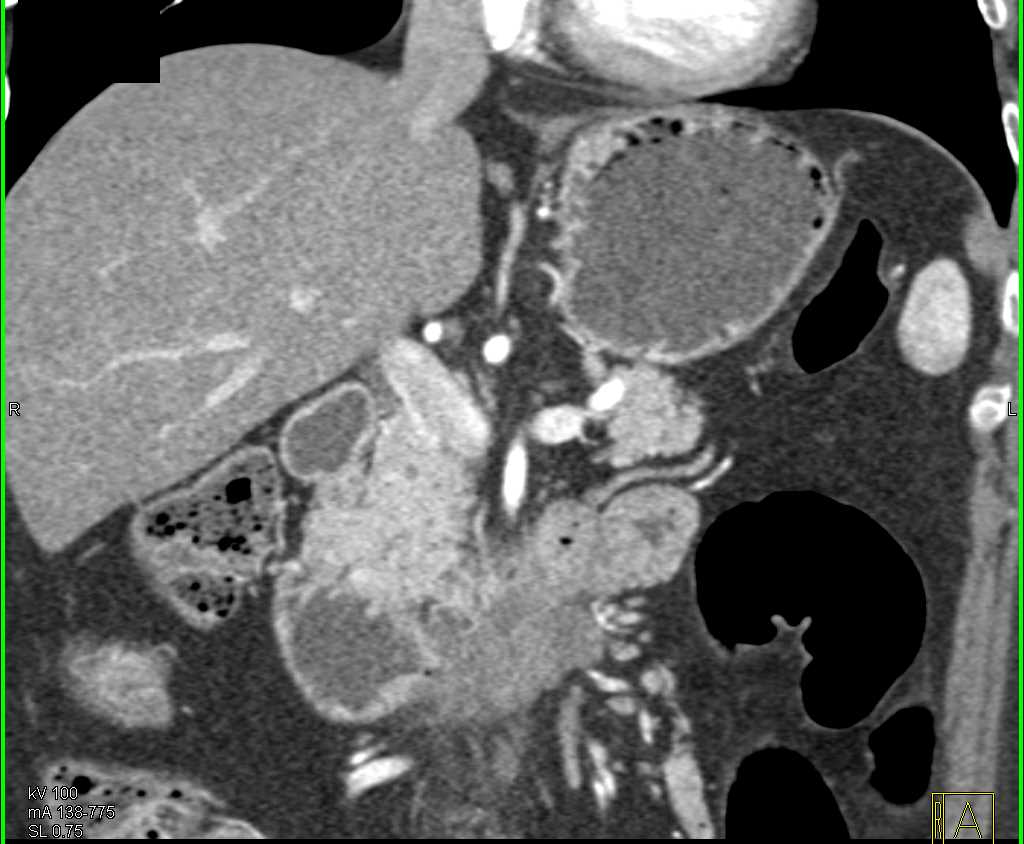

Duodenal Carcinoma with Obstruction